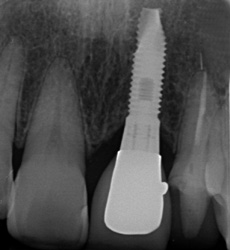

インプラント埋入のケース(前歯)

前歯が折れてしまい、ご来院されました。途中で折れてしまった歯の根を取り除き、インプラントを埋め込みました。前歯でも、ブリッジのように両隣の歯を削ることなく、見た目もキレイに修復することができます。